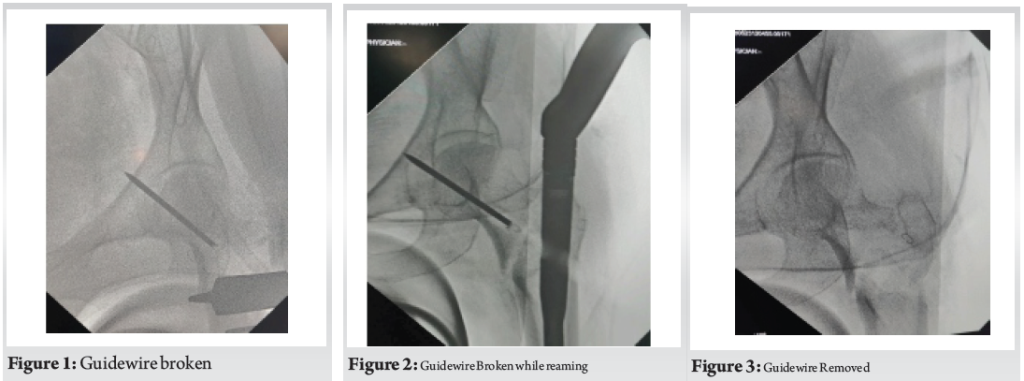

The surgical team proceeded with careful re-reaming through a new trajectory and completed the procedure using a slightly altered entry point and Proximal Femoral Nail was inserted (Fig. 4, Fig. 5). The patient was informed postoperatively, and serial radiographs showed no migration. She progressed to full weight-bearing by 10 weeks.